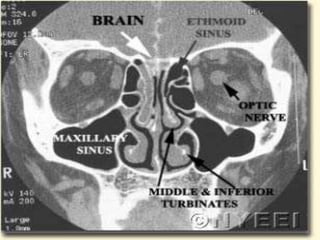

 Severe nasalcavity soft tissue thickening  Hypoattenuating mucosal thickening within lumen of paranasal sinus  Rapid aggressive bone destruction of sinus walls  Fungi can also spread along vessels with spread beyond the sinus with intact bony walls  Intracranial extension  cavernous sinus thrombosis  carotid artery invasion or occlusion

• 18.

 Unilateral ethmoidinvolvement with bone destruction, intraorbital spread and proptosis

 Better forevaluating intracranial and intraorbital extension ◦ Evaluate for inflammatory change in orbital fat and extraocular muscles ◦ Obliteration of periantral fat is a subtle sign of extension ◦ Leptomeningeal enhancement progressing to cerebritis and abscess